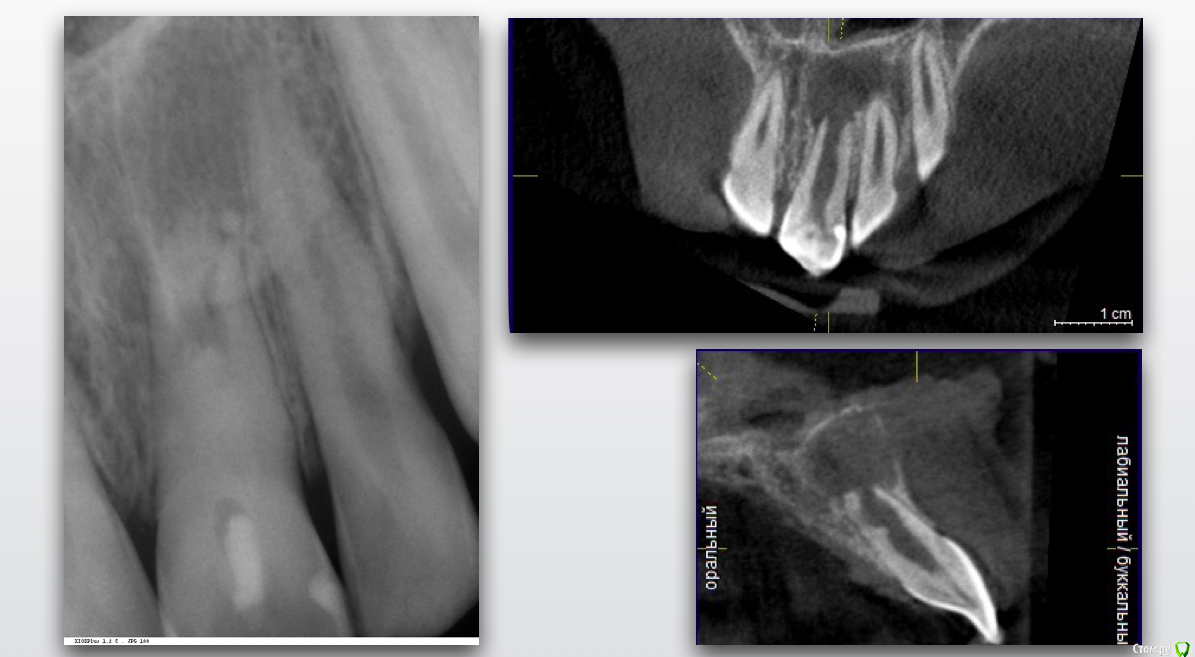

Гарриевич Опубликовано 5 февраля, 2019 Поделиться Опубликовано 5 февраля, 2019 Хочу рассказать одну маленькую историю об одной маленькой девочке, которая произошла не так давно, чтобы ее забыть, но и достаточно давно, чтобы убедиться в её хорошем конце.Утро у нас в клинике всегда начинается с пятиминутки, это время когда мы обсуждаем записанных на день пациентов и планируем лечение... то есть так должно быть, а по правде мы тратим эти 15 минут на обсуждение почему я опоздал, почему снова небритый и где вкуснее готовят кофе)Вообще душевный коллектив это здорово.Так вот на одной из пятиминуток главврач показал мне КТ 11-летней девочки с «кистой» верхнего центрального резца. До нас родители обращались в один большой московский Стоматологический ВУЗ и там и рекомендовали зуб удалить (киста же!), брекеты поставить, а после снятия брекетов и до 21 года ходить со съёмным протезом... у меня все... как вам план?Но есть стоматологи который читают современные книжки и есть пациенты которые читают, в правильных дозах, интернеты, и когда родители пришли к нам и услышали, что зуб не только не надо удалять, но ещё и можно вылечить, то обрадовались и остались лечиться. Всем пациентам довершим мне лечение зубов с «кистами»: спасибо! Прикладываю все усилия, чтобы каждый день это доверие оправдывать. Хорошего дня, Гарриевич. P.S. Разница между снимками 1,5 года 13 Ссылка на комментарий

Гарриевич Опубликовано 6 февраля, 2019 Автор Поделиться Опубликовано 6 февраля, 2019 Спасибо за кейс доктор , всегда приятно смотреть на борьбу со злом которая заканчивается победой "наших".. Расскажите немного о том какой природы была киста(диагноз так понимаю не гистологический) , и какими материалами работали в канале, заранее благодарю . спасибо)кистой я это называю исключительно в целях упрощения понимания пациентами. Конечно это банальный апикальный периодонтит с внушительных размеров резорбциейв канале мта и гутта (горячая) с эпоксидкой Ссылка на комментарий

Гарриевич Опубликовано 6 февраля, 2019 Автор Поделиться Опубликовано 6 февраля, 2019 Зачет! До какого расширяли?там до меня уже все само расширено былотолько ирригация с активацией 1 Ссылка на комментарий